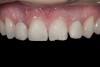

A 14-year-old patient presented to the office with his mother (Figure 1). His chief complaint involved the large spaces between the teeth created by his missing right maxillary lateral incisor and his small left maxillary lateral incisor. He desired to replace the missing tooth with an implant and create a beautiful smile. Upon examination, he was found to have a class I canine and molar relationship, but because he had a tooth size/arch size discrepancy and space distal to the right central incisor, the remaining incisors had drifted to the right. The left maxillary lateral incisor was peg-shaped and in a cross bite position. Studies have shown a clear association between congenitally missing teeth and reduced tooth size.59-62 Because he was only 14-years-old at the time and could not have implants placed until the cessation of growth (somewhere in the vicinity of 22 years old), he was sent to the orthodontist for alignment of the teeth.16,17 After 2 years of orthodontics, the appliances were removed, and his tooth coloration was improved using carbamide peroxide bleaching (Figure 2). Because some form of provisional needed to be placed until he was finished growing, a double-wing metal resin-bonded bridge was chosen. As discussed earlier, this is the ideal transitional prosthesis for patients that have congenitally missing maxillary lateral incisors. The benefits of this type of prosthesis include its ability to be removed and rebonded during the surgical phase of treatment and its ability to retain the roots in their proper position after orthodontic treatment.16 The final plan for the patient was to increase the width of the central and the maxillary left lateral incisor, utilizing porcelain laminate veneers to achieve the appropriate width/length ratio of 80%. A wax-up was created to idealize tooth size, a putty matrix was made from the wax-up to facilitate bonding of the incisors, and a non-precious, double-wing metal resin-bonded bridge was fabricated for lateral incisor replacement. Once the teeth were bonded to ideal size, the “Maryland Bridge” was fabricated from a polyvinyl arch impression with the newly bonded teeth (Figure 3). The metal frame was cast from a non-precious alloy to allow for fabrication of a very thin frame and to create a better surface for bonding. After sandblasting the internal aspect of the frame with CoJet™ silica (3M ESPE), accomplishing salinization, and executing cementation with a dual-cure resin cement, a fairly good adhesion to the frame was anticipated.29 The enamel surface was etched with phosphoric acid for 30 seconds, the primer (Single Bond Plus, 3M ESPE) was applied to both the internal surface of the sandblasted framework and the etched enamel, and the bridge was cemented with RelyX™ ARC (3M Espe) dual-cured resin cement (Figure 4 and Figure 5).

(2.) After orthodontic alignment of teeth and bleaching. Note alveolar deficiency in right lateral incisor site and diminutive left lateral incisor.

Figure 2

(20.) Facial view of final single-wing, modified zirconia resin-bonded bridges.

Figure 20

(21.) Smile view.

Figure 21